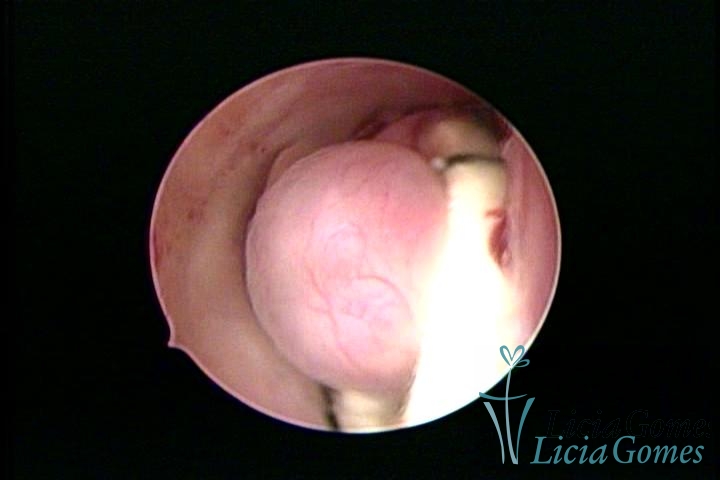

Uterine cavity with an old, folded IUD